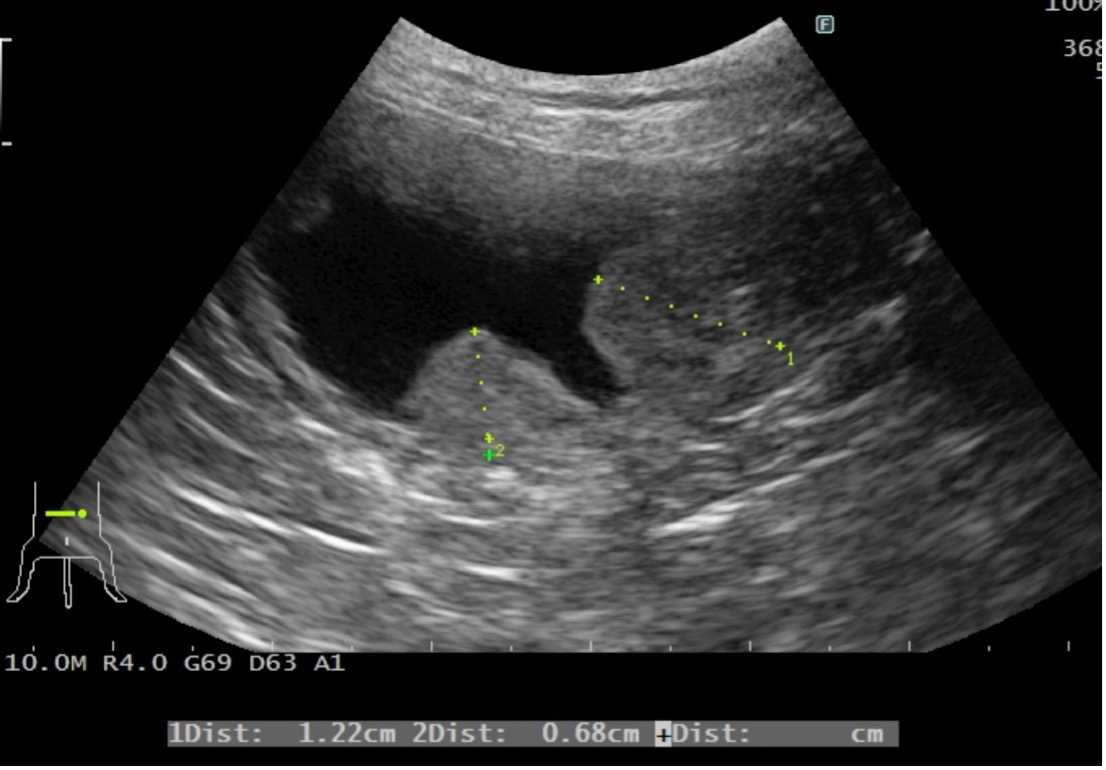

- 腹部の超音波検査